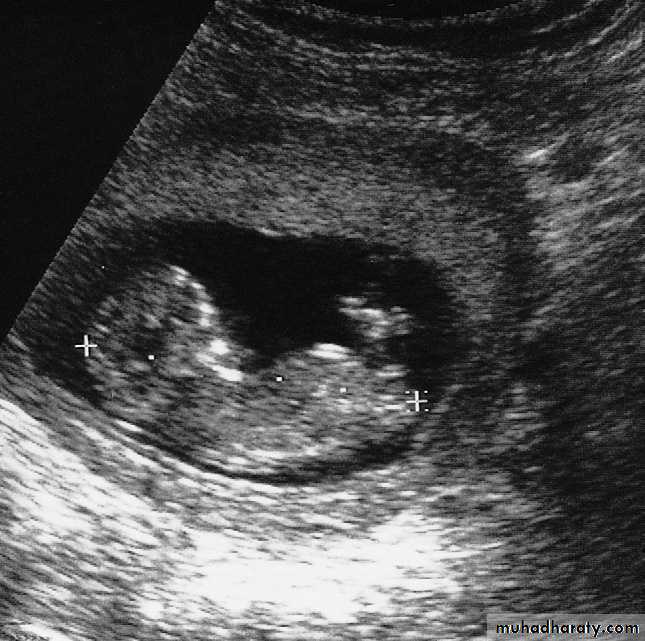

Ultrasound examination during early pregnancy may be undertaken trans abdominally or trans vaginally, although trans vaginal examination provides higher resolution.-The normal gestational sac is a small cystic structure lying within the uterine cavity, first seen at the fifth week following the last menstrual period.

-The developing fetus is seen by the sixth week and the fetal heart beat is visible by the seventh week.

The pregnancy can be dated by measuring the length of the fetus, between the seventh and 12th weeks of pregnancy .

-Multiple pregnancies can also be detected.

-Between 10 and 14 weeks, the nuchal translucency – fluid along the back of the fetal neck – may be measured.This technique can be used to detect Down’s syndrome and some other chromosomal or fetal abnormalities.